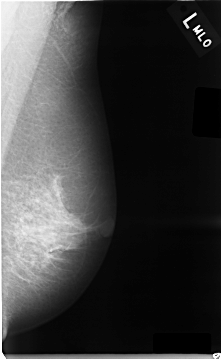

C_0005_1.LEFT_MLO

LEFT_MLO LINES 4656 PIXELS_PER_LINE 2872 BITS_PER_PIXEL 12 RESOLUTION 50 NON_OVERLAY